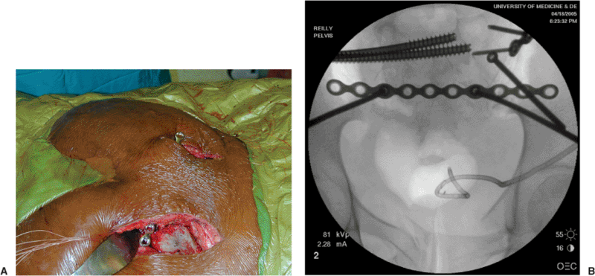

Figure 40.7. A. The osteotome is introduced ventral to the multifidus and utilized to osteotomize the spinous process of S2. B. Fluoroscopic image of in-place osteotome.

|

Figure 40.8. A. The osteotome has been exchanged for the straight pelvic-reconstruction plate. B.

The plate has been secured to each posterior superior iliac spine by means of a 4.5-mm screw placed parallel to the greater sciatic notch between the tables of the iliac wings. |